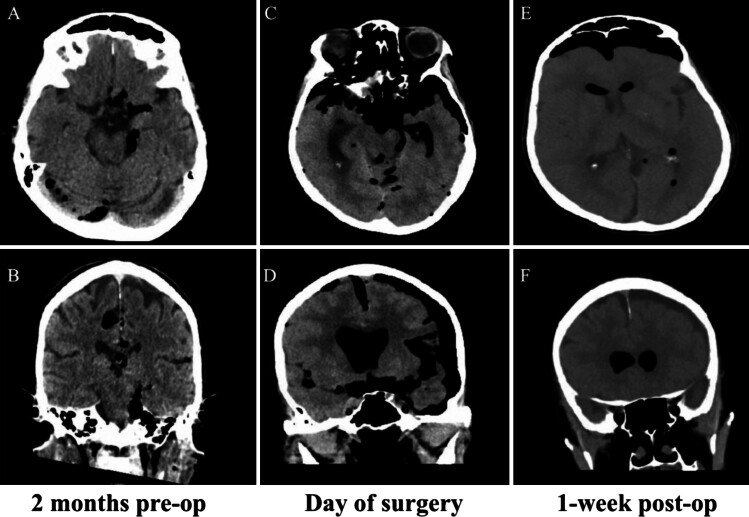

Observations: A 76-year-old female presented to the authors' institution with rapidly progressing spontaneous pneumocephalus. This case is unique in that the patient's pneumocephalus continued to expand without any radiological indication of extracranial CSF, leading us to believe that the CSF was intermittently leaking through the eustachian tube and passing down the patient's oropharynx. Given the presumed pathway, an initial conservative surgical approach was chosen for this patient's spontaneous pneumocephalus instead of the traditional middle cranial fossa or transmastoid approach.

Lessons: To repair the leak, the authors attempted a more conservative approach involving closure of the external acoustic meatus and obliteration of the eustachian tube. A few studies using a similar procedure reported a lower risk of complications and reduction in postoperative CSF leaks. https://thejns.org/doi/10.3171/CASE24834.